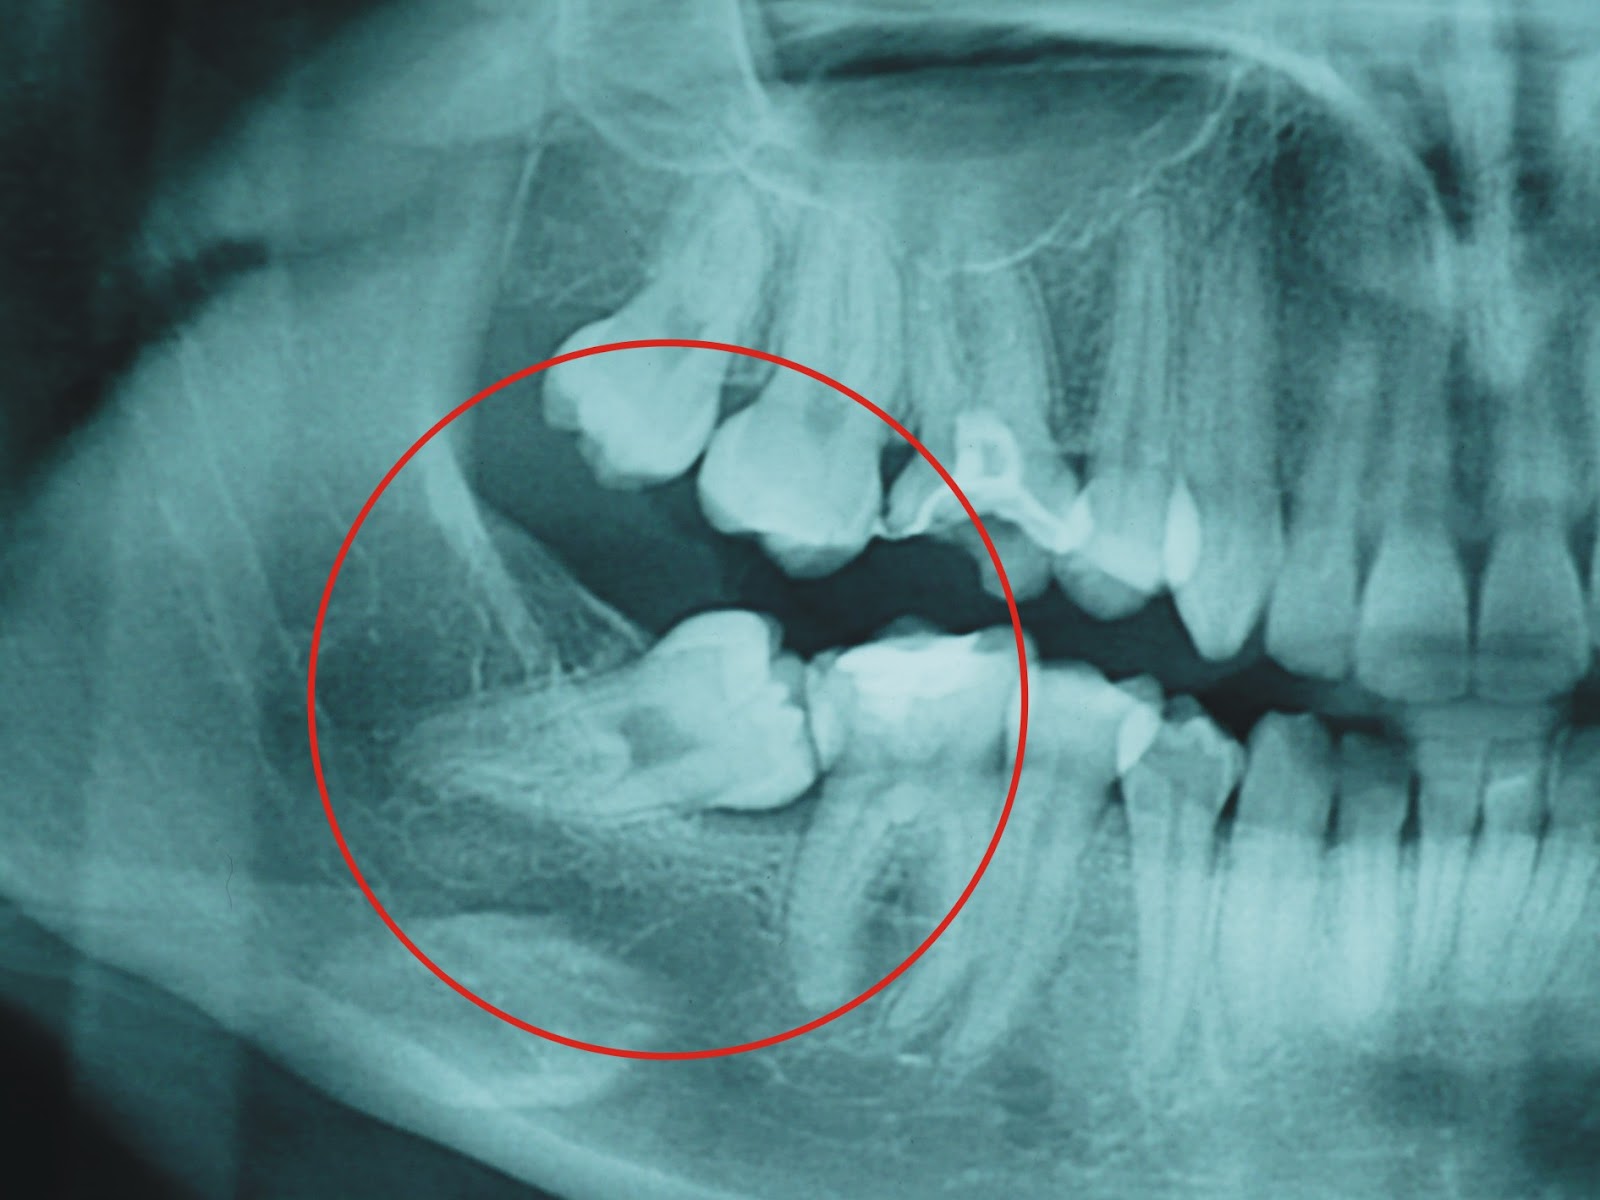

Por lo general, le solicitará una radiografía panorámica u ortopantomografía para valorar su caso; y en caso de ser necesario complementar el estudio podría solicitarle un CBCT (Tomografía Computarizada de Haz Cónico).

Muchas personas tienen las muelas del juicio impactadas o retenidas; lo que les puede producir:

• Daño de los dientes adyacentes o del hueso de los maxilares

• Formación de quistes alrededor de las muelas del juicio